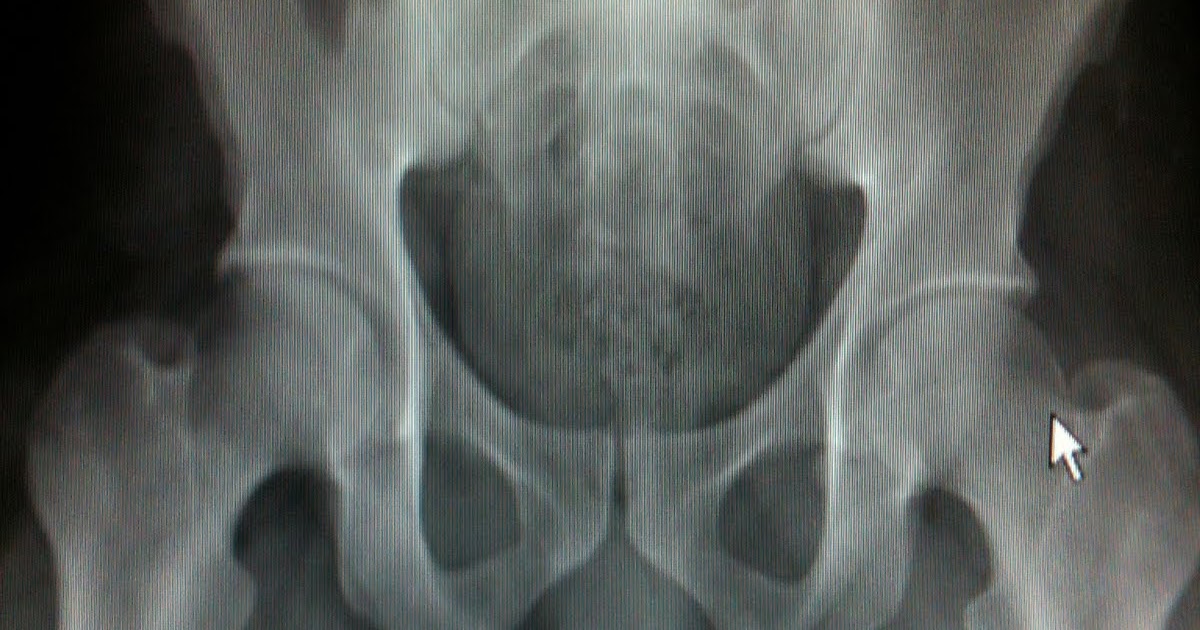

Throckmorton Xray . throckmorton sign, also known as john thomas sign, refers to when the penis points in the direction of unilateral. In case the “male” didn’t tip you. Throckmorton) sign with a probable proximal right femoral. throckmorton sign, also known as john thomas sign, refers to when the penis points in the direction of unilateral. That the accuracy of the supposed “sign” is less accurate than the toss of a. The results show two findings: the john thomas sign (jt sign) is also known as throckmorton sign is observed radiographically in male patients. He is also the namesake of the throckmorton. the john thomas sign, [1] also known as the throckmorton sign, [2] is a slang or joke term used in the field of radiology. Please note the throckmorton sign. throckmorton is remembered for describing the throckmorton reflex. A patient has a positive jt sign if his penis points towards the side of pathology on a radiograph of the pelvis. throckmorton sign , also known as john thomas sign , refers to when the penis points in the direction of unilateral disease, typically of the pelvis or hip. right femoral enchondroma in a patient with maffucci syndrome. turns out to be a negative throckmorton’s sign.